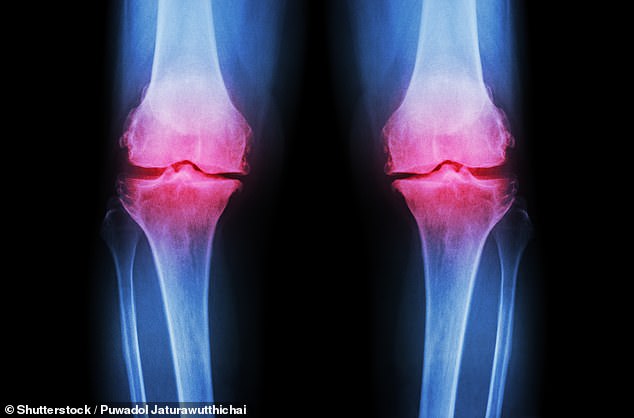

Osteoarthritis affects over 10 million people nationwide, with symptoms ranging from persistent joint pain to severe stiffness that limits daily activities. Current treatments often rely on painkillers or physiotherapy, both of which come with limitations. Medications can lead to gastrointestinal issues or dependency, while physiotherapy demands consistency and access to resources many struggle to maintain. Now, this study raises a compelling question: what if the answer to managing osteoarthritis lies not in pharmaceuticals but in something as simple as a spoonful of fibre?

The research followed 117 adults with knee osteoarthritis participating in the INSPIRE trial. They were randomly assigned to receive either inulin, physiotherapy, a combination of both, or a placebo. The results were striking: participants taking inulin alone experienced measurable reductions in pain sensitivity and improvements in grip strength—metrics that have long been linked to overall physical health. One participant, a 68-year-old woman who had struggled with daily tasks for years, reported being able to walk without a cane after six weeks of taking the supplement. Could this be the first step toward a more holistic approach to arthritis care?